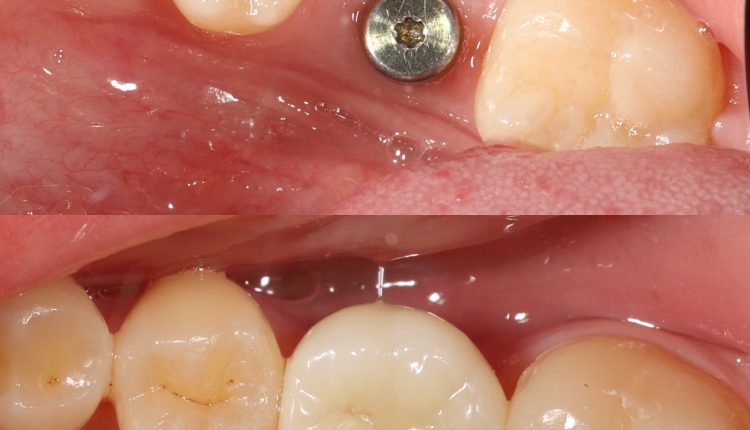

Зубний імплант складається з трьох частин:

• Титановий стрижень — замінює корінь зуба та вживлюється у кістку.

• Абатмент — з’єднувальний елемент між імплантом і коронкою.

• Коронка — видима частина, що повторює форму й колір натурального зуба.

3. Остеоінтеграція — період зрощення імпланта з кісткою, що триває 2–6 місяців.

4. Установка абатмента та коронки — завершальний етап, після якого пацієнт отримує міцний і повноцінний зуб.